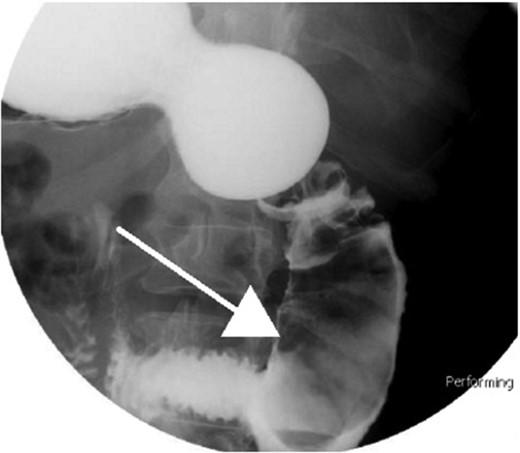

Small bowel series showing duodenal filling defect (anterior view).

With regard to diagnostic workup, the literature has described cases with similar results to ours. Small bowel contrast studies frequently show smooth-walled polypoid filling defects within the duodenal bulb, and CT imaging is useful for delineation of adjacent structures including the common duct and pancreas [1]. Moreover, similar to the pathological results found in our patient, upper endoscopy biopsies are often equivocal as they are submucosal-based lesions [1]. The most useful diagnostic study, however, is endoscopic ultrasound, which may help distinguish the consistency and bowel layer of origin [2, 6], which unfortunately was not available at our institution.